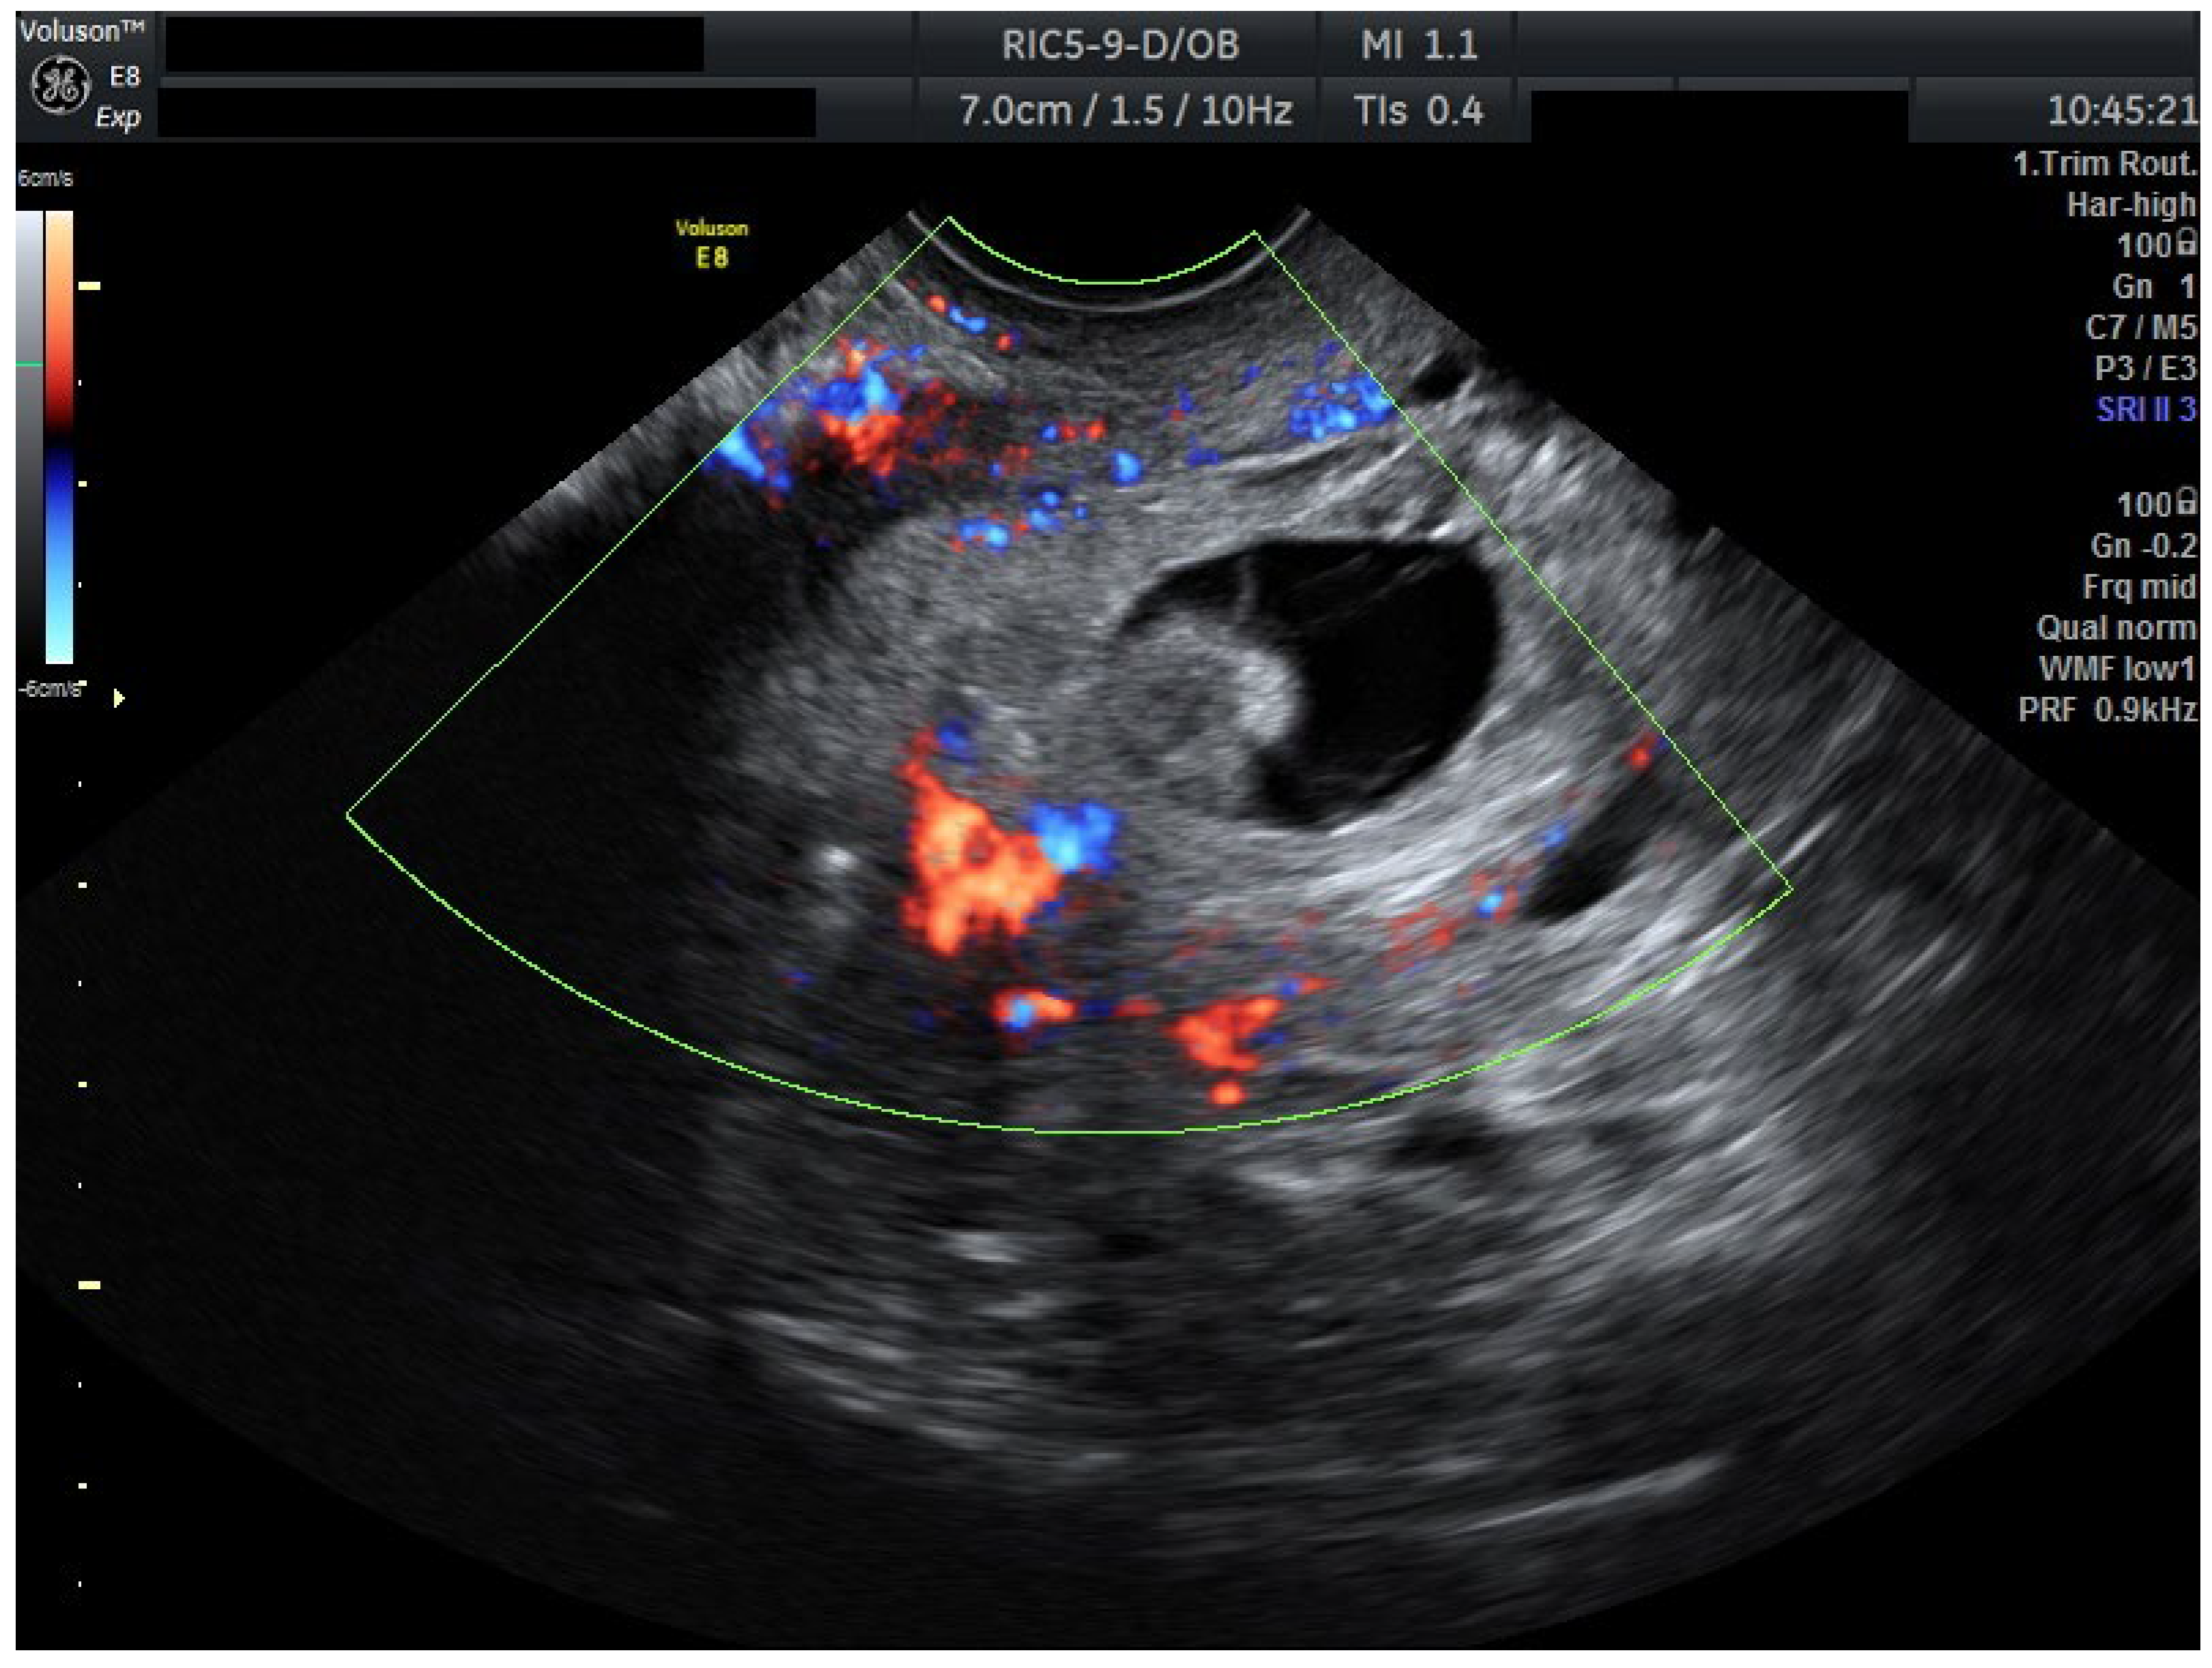

To ensure complete trophoblastic regression in both pregnancies, systemic methotrexate 100 mg was administered intramuscularly at this time (Day 4). A follow-up ultrasound at 48 h (Day 6) confirmed the absence of cardiac activity in both gestations, disorganized gestational sacs, consistent with successful termination. Cervical stromal vascularity identified on color Doppler was suggestive for trophoblastic remnants (Figure 2).

Figure 2.

Ultrasound results after methotrexate 100 mg (Day 6). Transvaginal ultrasound evaluation: both sagittal view through the uterus and transverse view through the cervical canal. A total of 48 h after methotrexate 100 mg (Day 6): both embryos without cardiac activity. Cervical stroma with vascularity. Patient information is anonymized.

Serial ultrasound over 72 h documented progressive closure of feeding vessels and reduction in cervical stromal vascularity.